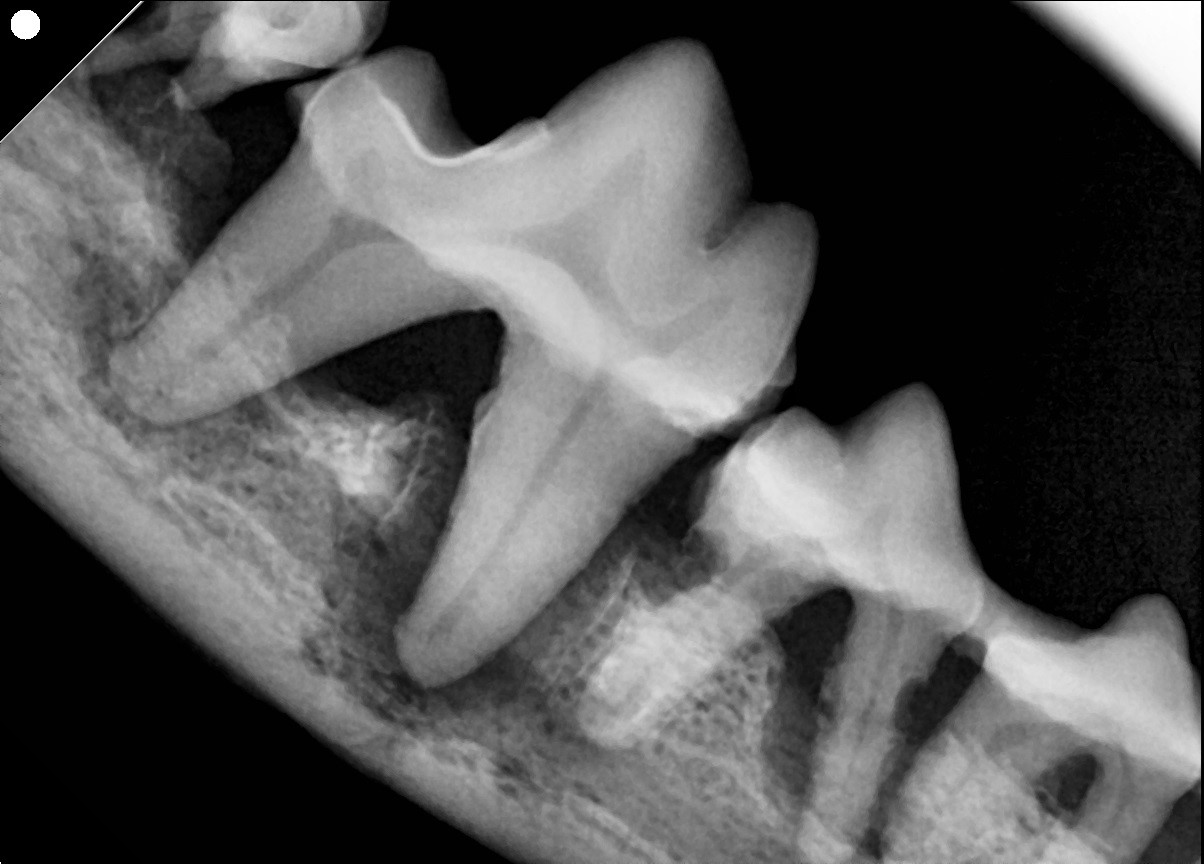

Periodontal Disease

First molar of a dog showing advanced periodontal disease. The black around the tooth roots represents a complete loss of bone holding the tooth in place.